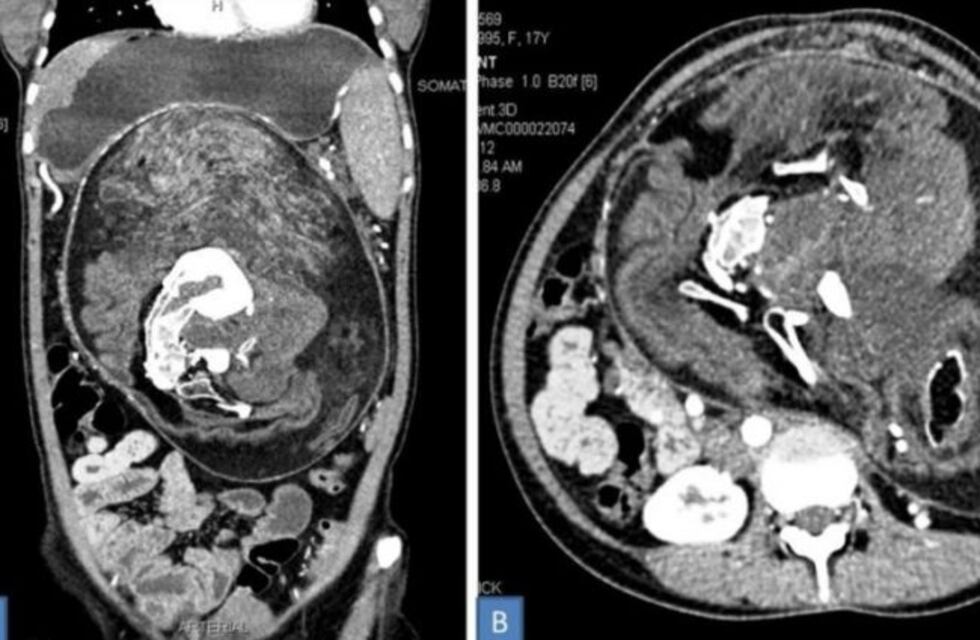

Luego de 5 años, los médicos sostenían que se trataba de un tumor pero al hacerle una tomografía computarizada algo les llamó la atención: el bulto tenía cabello, dientes, costillas, hueso largos y vértebras.

Se trataba de un gemelo que no se desarrolló durante el embarazo y fue "absorbido" por la mujer mientras crecía en la panza de su madre. Las imágenes detallan que el feto medía 36 x 16 x 10 centímetros, el más grande hasta el momento.